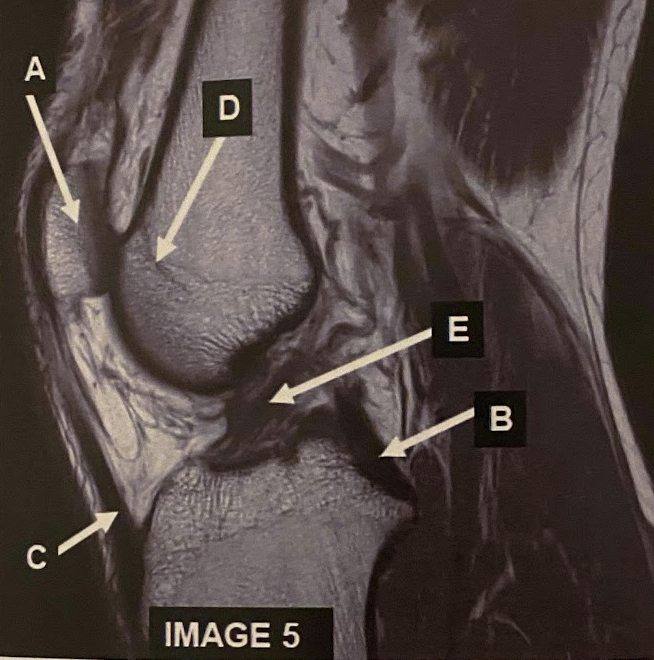

20

What anatomy does letter A demonstrate?

A

Patella

21

Q

What anatomy does letter B demonstrate?

PCL

22

What anatomy does letter C demonstrate?

Patellar Tendon

23

What anatomy does letter D demonstrate?

Femoral Condyle

24

What anatomy does letter E demonstrate?

ACL